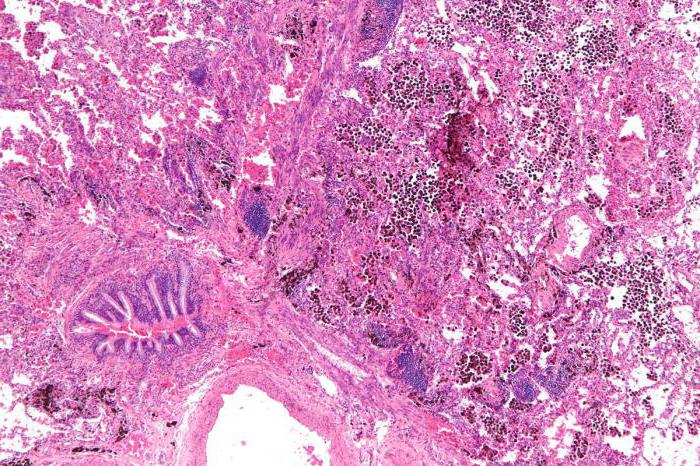

К наиболее часто встречающимся легочным патологиям, которые осложняются кровотечением, относят туберкулез, рак и бронхоэктатическую болезнь. Все эти недуги очень опасны и требуют длительного лечения в специализированных учреждениях. Легочное кровотечение свидетельствует о прогрессирующем кавернозном туберкулезе. Зачастую оно возникает на фоне приступа кашля.

При раке легкого кровотечение свидетельствует о распаде опухоли и повреждении сосудов. Остановить его бывает очень сложно. Особо опасно профузное кровотечение, при котором выделяется 500 мл биологической жидкости. Подобный симптом может закончиться летальным исходом. Помимо того что идет кровь изо рта, пациенты жалуются на затруднение дыхания, кашель, потерю веса.

Кровотечение при раке легких: особенности

Рак легкого считается одной из самых распространенных онкологических патологий среди мужчин. В большинстве случаев он развивается на фоне хронических воспалительных болезней дыхательной системы. Главным фактором риска считается злоупотребление табакокурением на протяжении долгих лет. Источником кровотечения при раке являются поврежденные сосуды или сама опухоль, находящаяся в фазе распада.

Признаками заболевания является длительный сухой кашель, не поддающийся лечению. Через несколько месяцев присоединяется кровохарканье. Помимо этого отмечается лихорадка, выраженная слабость, одышка и потеря веса. Кровотечение может иметь различный объем: от малого (50-100 мл) до профузного (более 0,5 литра). В большинстве случаев оно сопровождается кашлем. При этом имеется высокий риск аспирации и развития геморрагического шока.